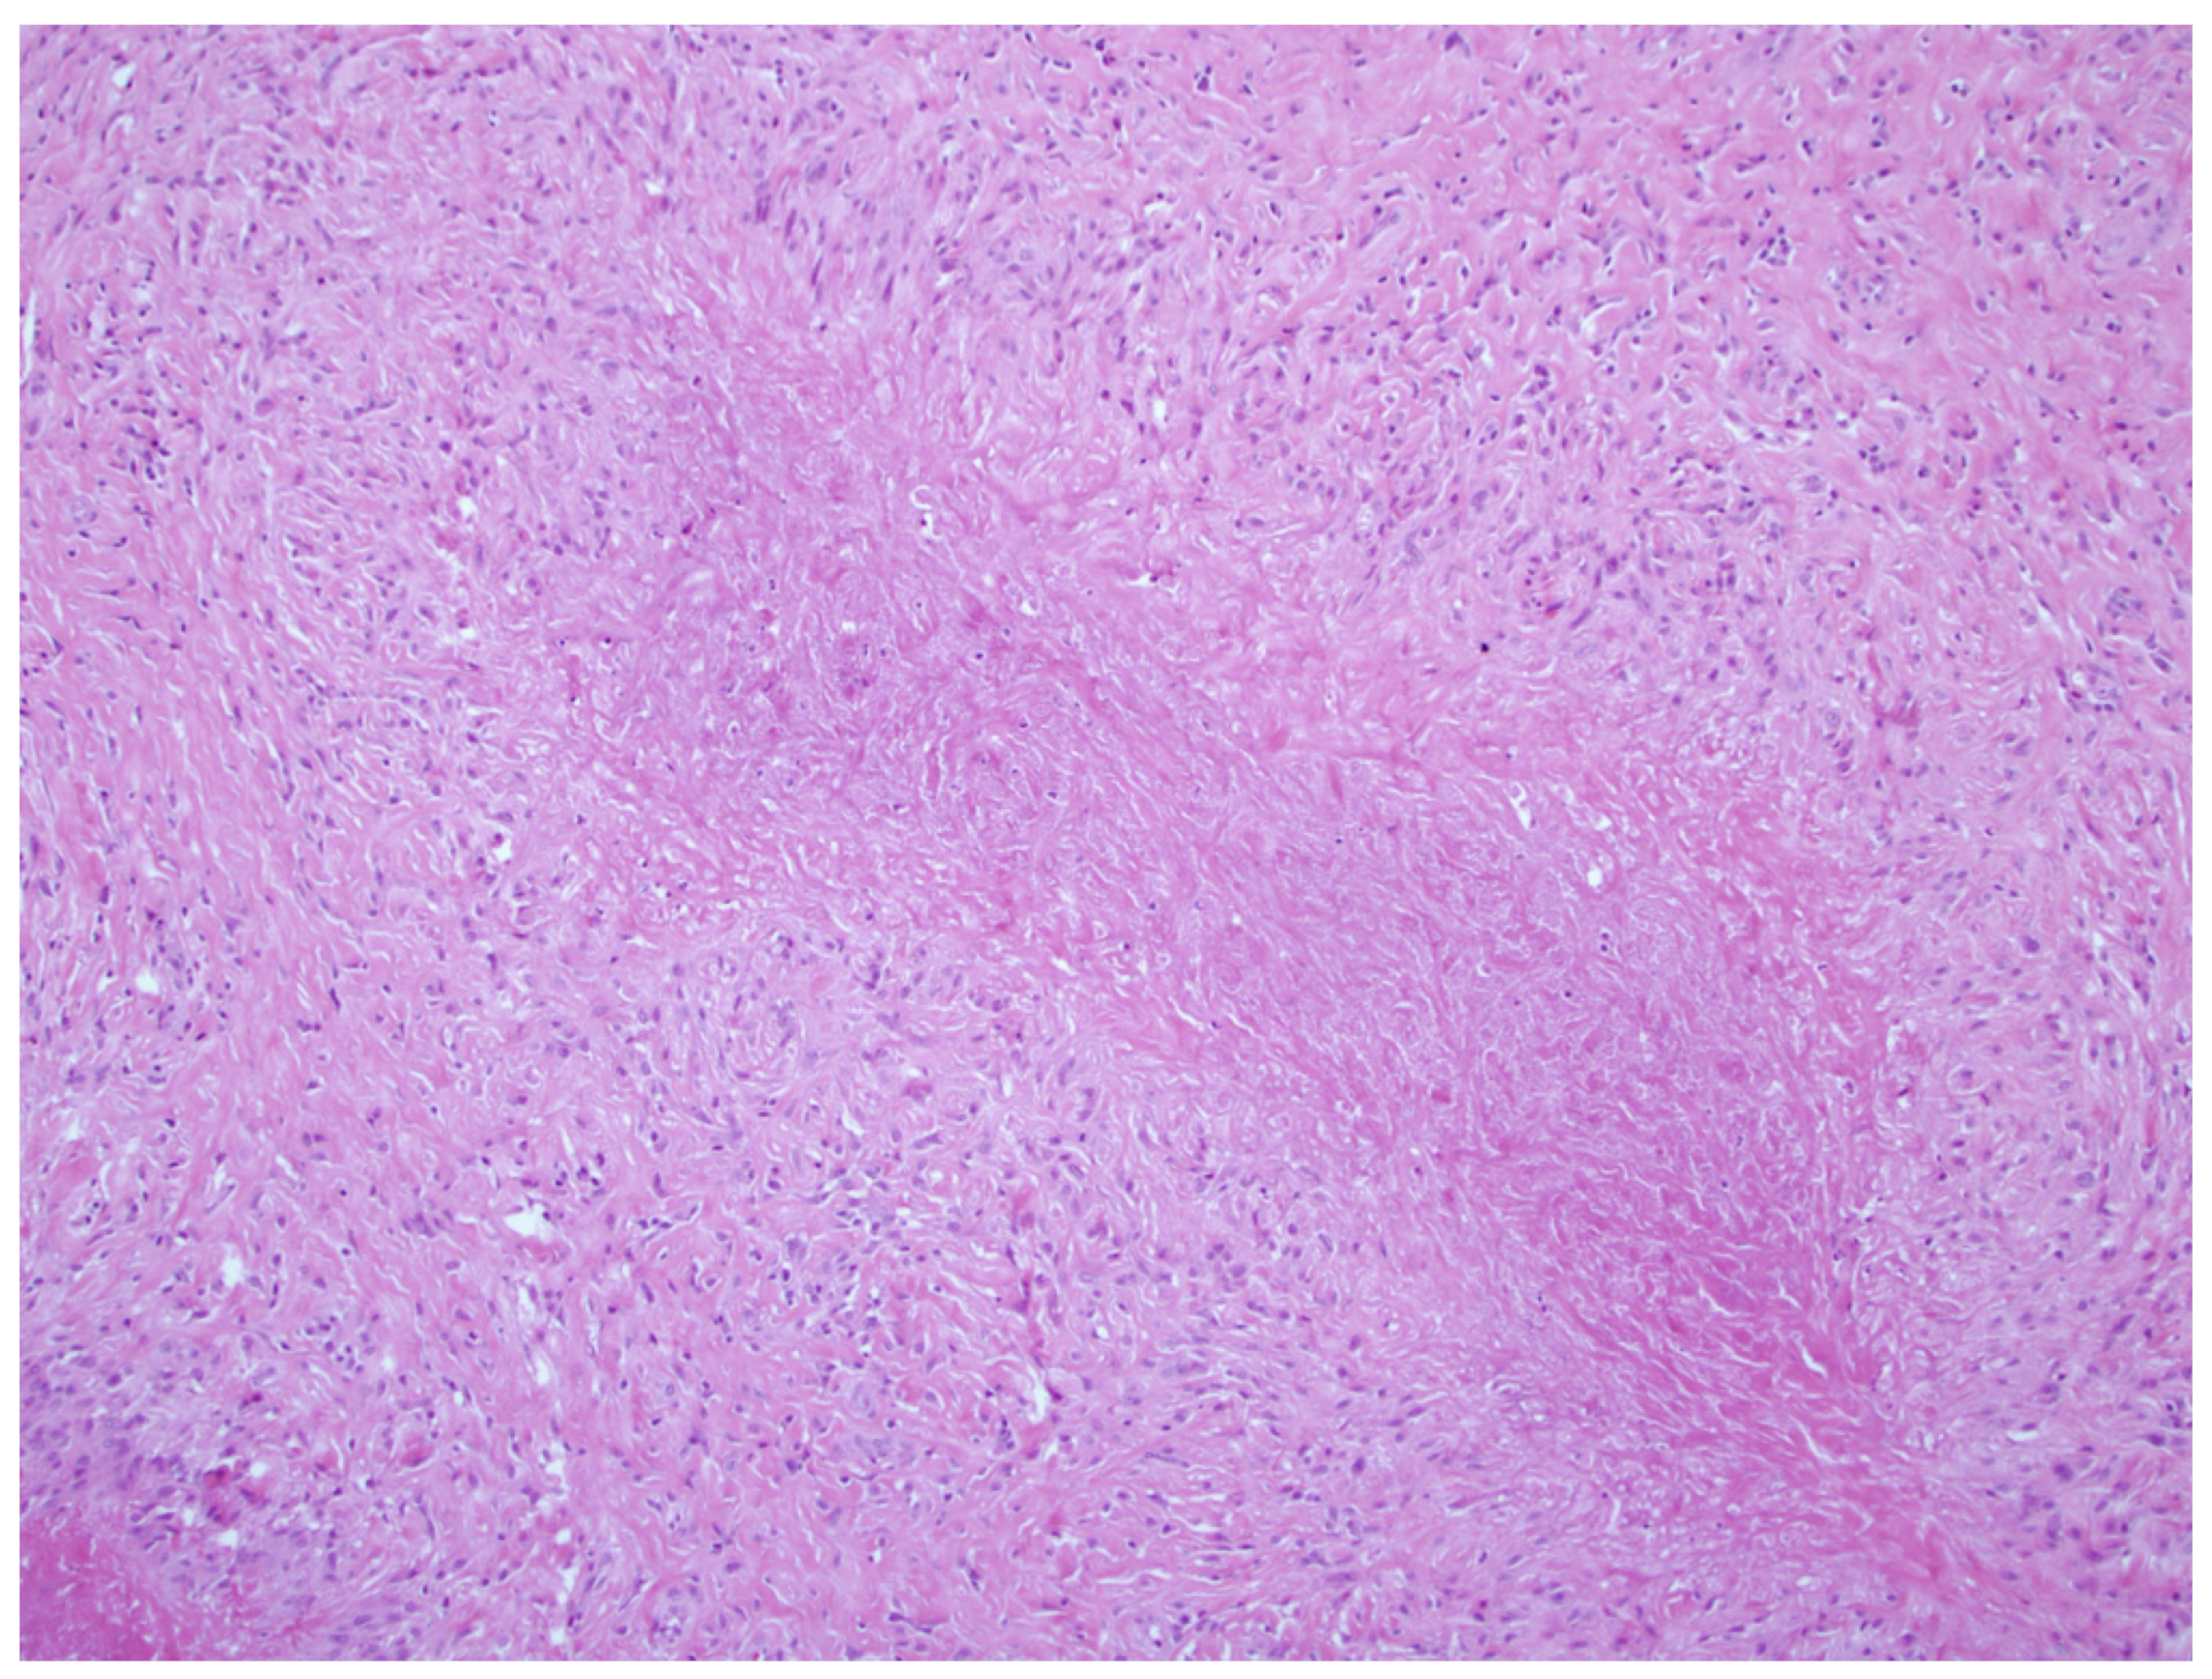

3.1. Nodules

3.1.1. Rheumatoid Nodules